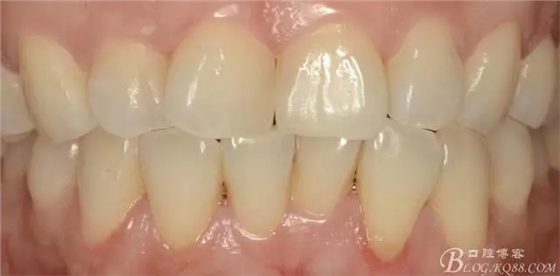

一周后復(fù)診即刻照:

(脫礦情況好轉(zhuǎn),但仍有部分釉質(zhì)仍未恢復(fù))

此案例中,酸蝕出現(xiàn)過度后,我沒有予以含氟涂料進(jìn)行處理,所以通過這個(gè)案例,驗(yàn)證了上述的學(xué)者的部分研究,即使修復(fù)后有脫礦,可不予處理,其在口腔中通過表面摩擦及口腔唾液環(huán)境中再礦化這兩種途徑,輕度脫鈣浸蝕的恢復(fù)。